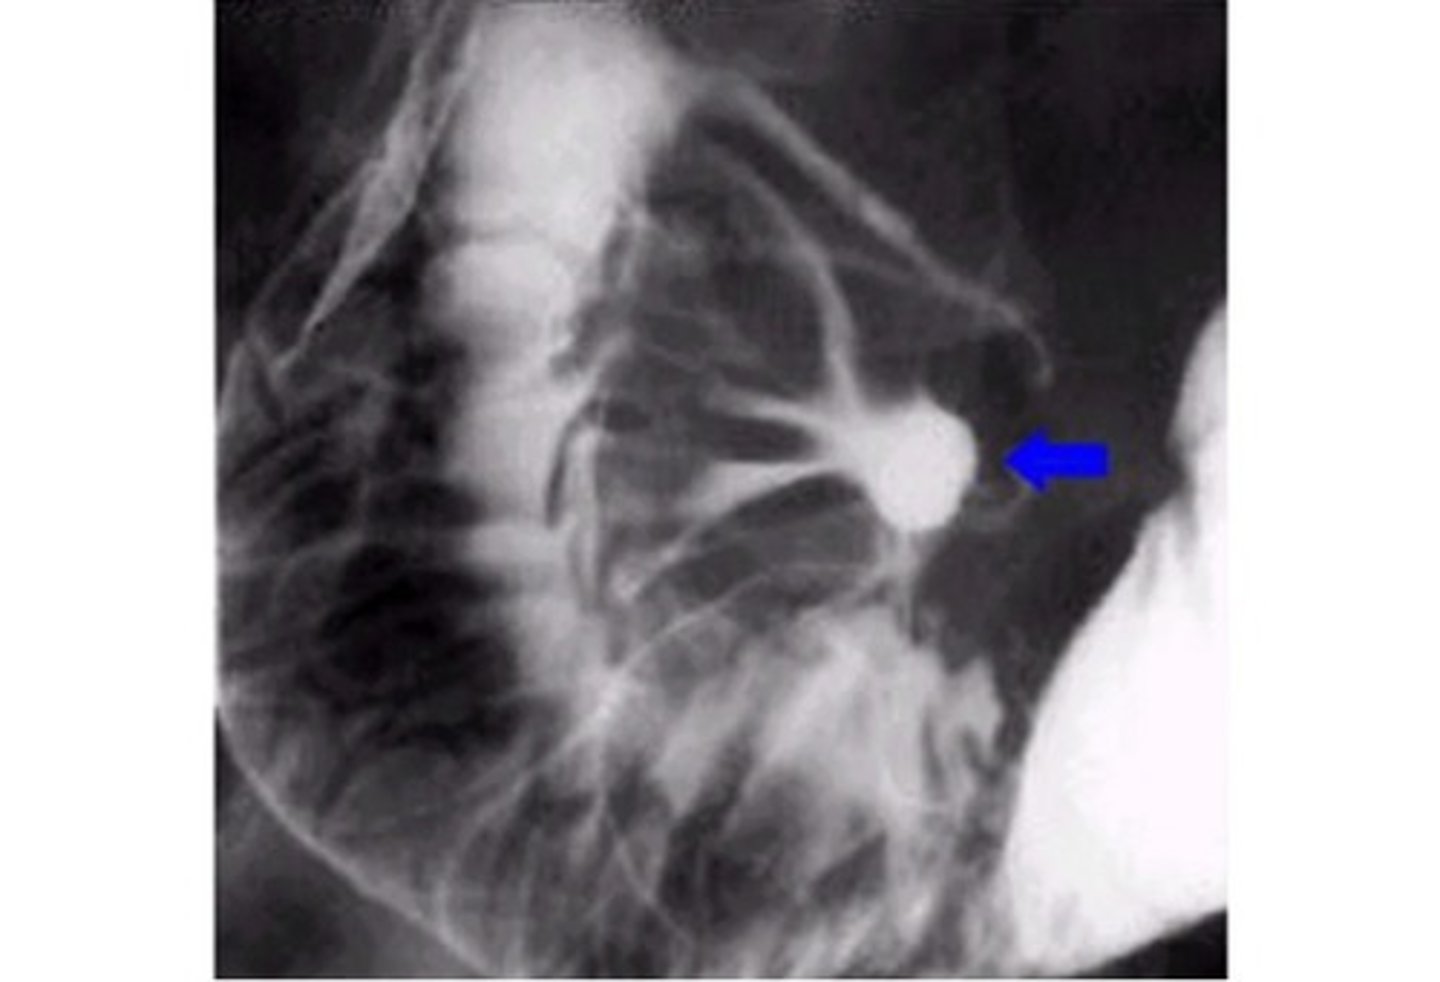

ulcer

Ulcer (pic 2)